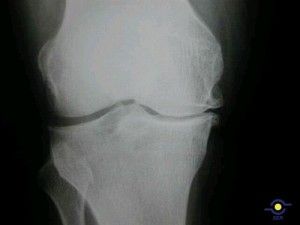

El 70% de los pacientes con artrosis se ven impedidos en algún grado para llevar a cabo sus actividades cotidianas

Por |2019-11-22T19:38:59+02:00septiembre 13th, 2013|3ª Edad, Enfermedades, Esqueleto, Medicamentos, Ortopedia|Comentarios desactivados en El 70% de los pacientes con artrosis se ven impedidos en algún grado para llevar a cabo sus actividades cotidianas

artrosis-rodilla

Una encuesta realizada a 500 pacientes artrósicos de Andalucía, Asturias, Cataluña, Galicia, Madrid y Valencia, pone de relieve que el 1,3% afirma estar ‘totalmente impedido’; el 20,5%, ‘bastante impedido’ y el […]